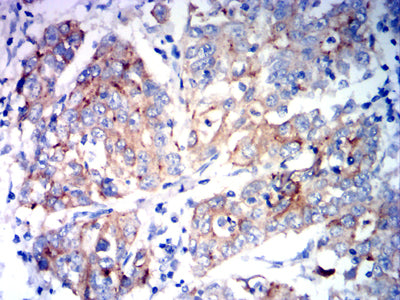

Immunohistochemical analysis of paraffin-embedded human esophageal cancer tissues using KCNK1 mouse mAb with DAB staining.

Immunohistochemical analysis of paraffin-embedded human stomach cancer tissues using KCNK1 mouse mAb with DAB staining.